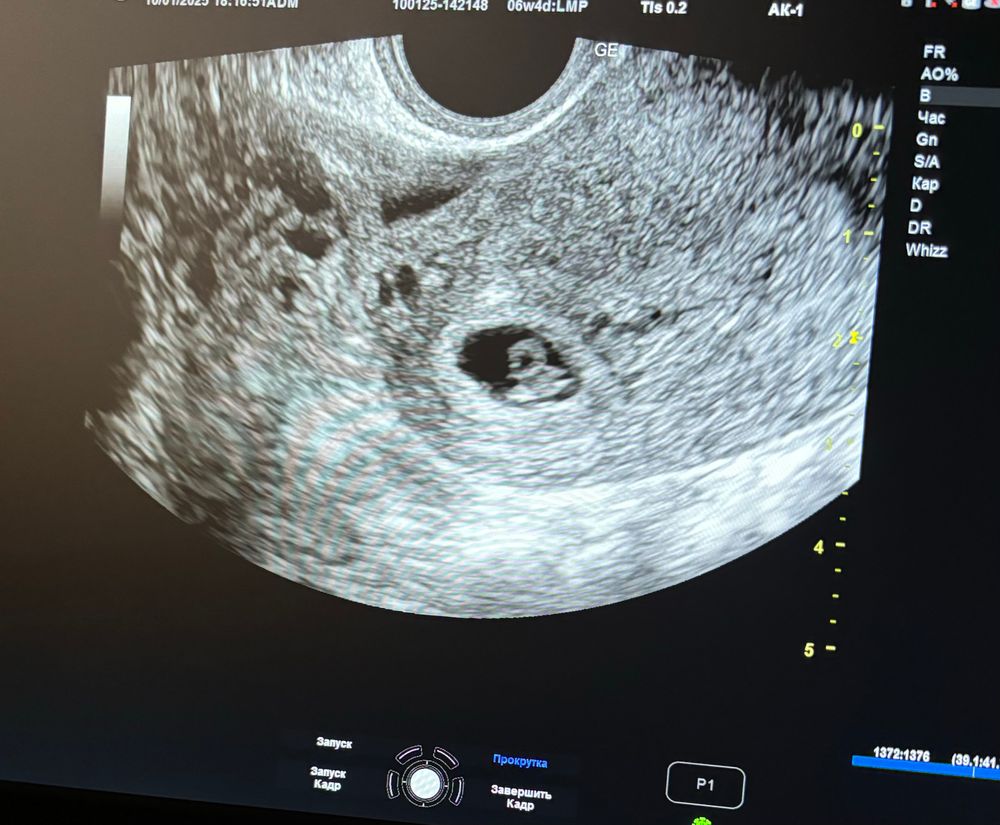

УЗИ 6 недель 4 дня

Пошла я на более чувствительный аппарат в поисках своего эмбриончика (в 5/5 его не увидели) и таки нашла.

Радости нет предела, девочки. Все размеры соответствуют срокам. Сердечко даже дали послушать ! Я была в восторге! Как теперь закрепиться в этих положительных эмоциях?